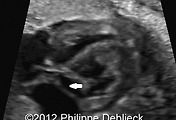

3. It lies adjacent to and slightly posterior to the mitral valve annulus within the atrio-ventricular groove.

4. The entire length of the coronary sinus can be demonstrated from the lateral free wall of the left ventricle to the ostium. The ostium of the coronary sinus is found in the same plane as the inter-atrial septum, just posterior to the crux.

1. Examine the heart in the lateral 4-chamber view (most favorable insonation angle to study blood flow across the coronary sinus).

2. By tilting the transducer caudally from the level of the foramen ovale, flow along the axis of the atrioventricular sulcus is representative of coronary sinus flow.

3. The coronary sinus blood flow can be seen entering the right atrium at the inferior edge of the foramen ovale just above the tricuspid valve. Blood flow is directed towards the right atrium.